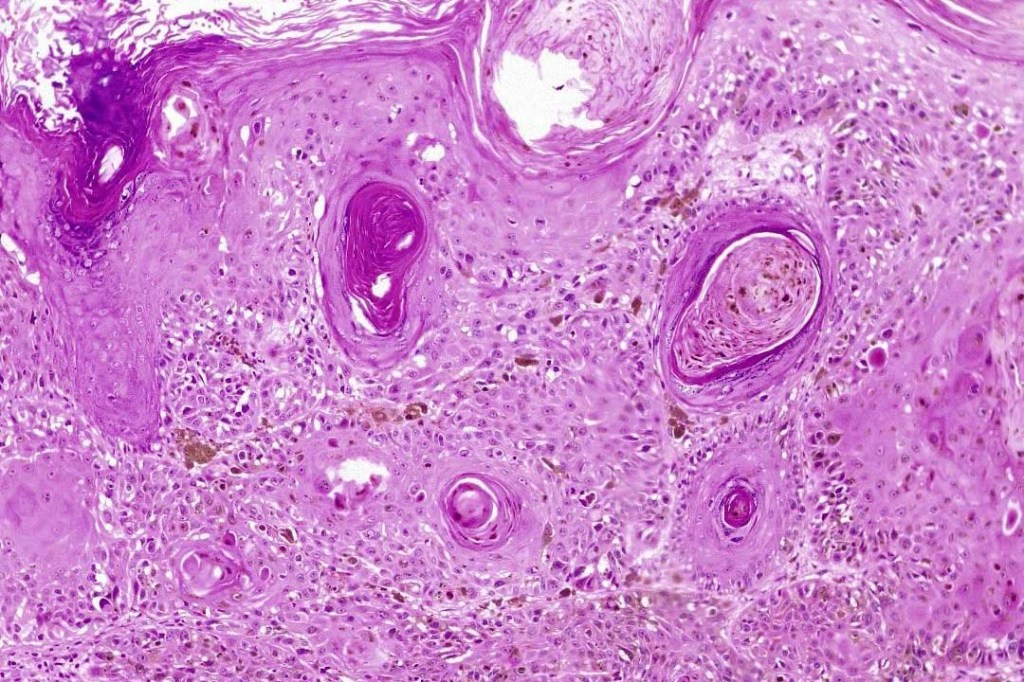

An exceedingly rare collision tumor composed of an admixture of squamous cell carcinoma/basal cell carcinoma/trichoblastoma respectively and melanoma. Although most appear to have behaved in a benign fashion, a malignant basomelanocytic tumor is illustrated below. More cases will be need to be stidies/published before the true biological behavior of this group of tumors can be satisfactorily elucidated. I think that complete excision should be the rule and a careful follow-up recomended.

Basomelanocytic tumor